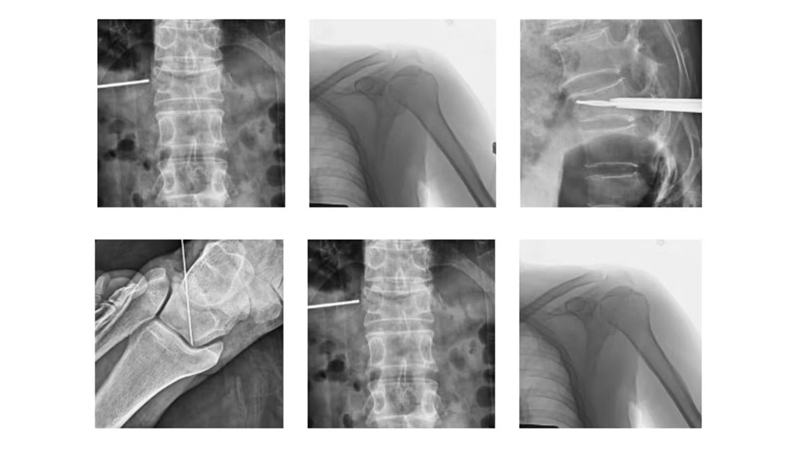

Característica: Integra detectores de alta resolución y tecnología avanzada de procesamiento de imágenes para proporcionar vistas quirúrgicas de alta definición en tiempo real, asegurando imágenes claras y detalladas. Su estructura única de gran apertura y su sistema de control flexible le permiten rotar fácilmente en múltiples ángulos en diferentes posiciones. Ofrece versatilidad para una variedad de procedimientos clínicos, incluidos procedimientos ortopédicos, vasculares, traumatológicos, de columna, para el tratamiento del dolor, urológicos, cardíacos y otros.

Sistema de brazo en C digital de alta frecuencia